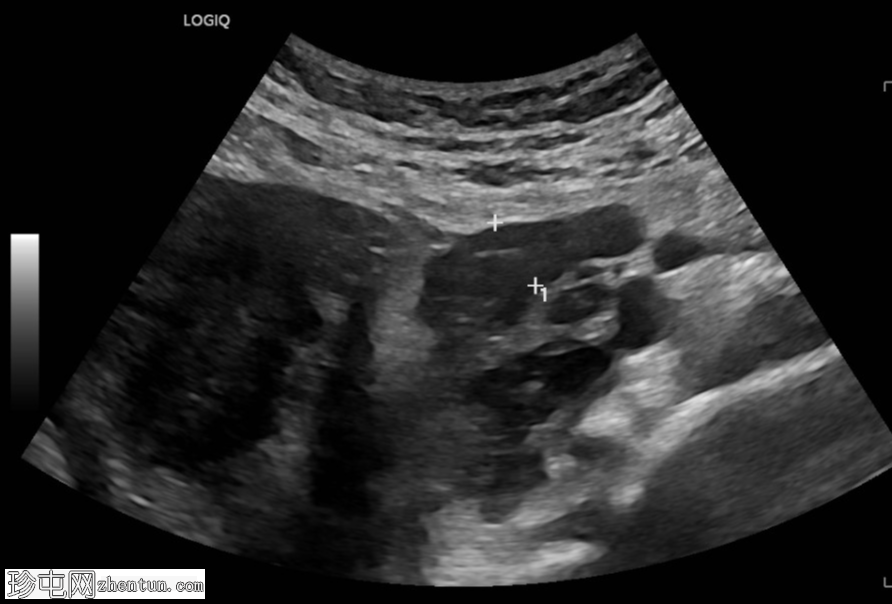

超声检查

斜切面

左侧卵巢明显增大,可见一囊肿,大小约3.2 x 2.3 cm,呈火环征,可能为黄体囊肿。左侧卵巢与子宫之间可见一管状结构,直径约1.3 cm,内含浑浊液体,未见血管,最可能为输卵管积血。以上特征提示可能为左侧异位妊娠。

未见宫内妊娠囊。